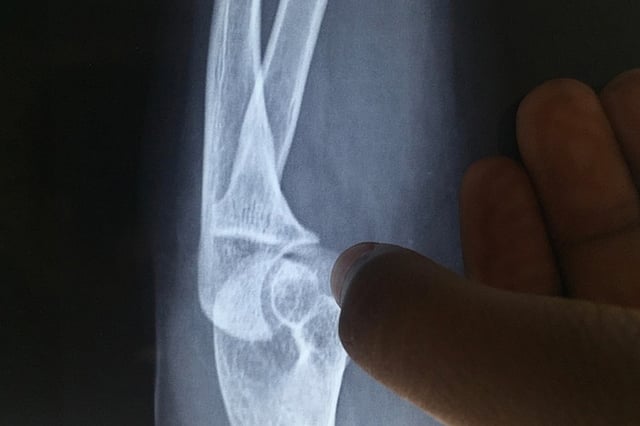

Medical investigations led doctors to conclude that Shanti had extremely low bone density, which was making her more prone to sustaining fractures from even minor impact injuries. She isn’t alone. Each year scores of women are treated for fractures, while many of them brush off injuries as related to “old age”, doctors state that post-menopausal women are at particular risk of osteoporosis.

Osteoporosis is a term which literally means “porous” bone. As the name suggests, it is a result of loss of bone density as a result of which the bones become brittle and fragile, putting them at risk of fracturing easily. Many women may develop osteoporosis around menopause, for which certain precautionary measures should be taken.

What can happen if osteoporosis goes undetected? According to Dr Krishnan M, an orthopedician from Bengaluru, someone with osteoporosis is at risk of developing fractures due to physical injuries. Areas such as the spine or the head of the thigh bone (femur) are the areas that are most commonly prone to fractures.